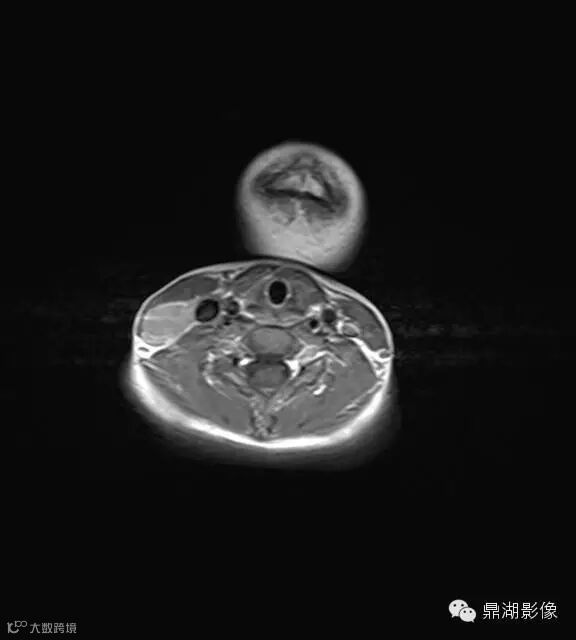

上海儿童医院韩燕乔教授诊断:考虑淋巴结炎 ,可见杯状分层,液液平

神经源性肿瘤:肿块较大,信号常不均,有人认为肿瘤位于屈肌的区域或伴有肌肉萎缩强烈提示神经源性肿瘤。

淋巴结核:多融合成团,呈花环状,边缘强化,淋巴结内见到斑点状钙化有助结核的诊断。

猫抓病性淋巴结炎:不少医生诊断为猫爪病,该病确实很接近。均为炎性改变,脓肿、坏死形成时,虽呈边缘强化特点,但多个淋巴结间界限清楚,无融合改变,内也无斑点状钙化。